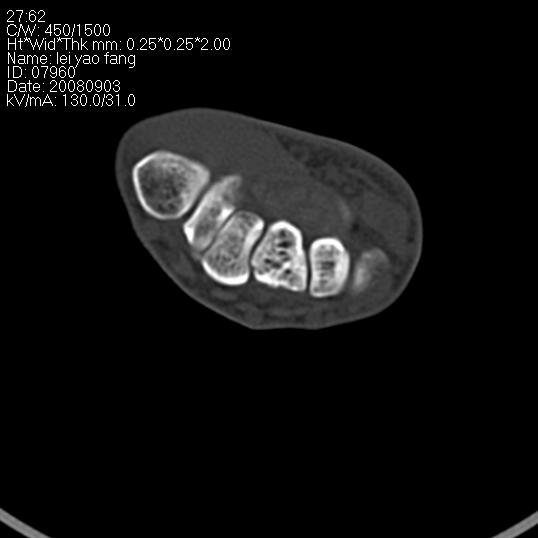

以下是引用杀毒软件在2008-9-4 17:41:00的发言:[br]考虑----舟骨囊肿